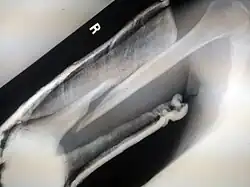

(a) closed fracture

(b) open fracture

(c) transverse fracture

(d) spiral fracture

(e) comminuted fracture

(f) impacted fracture

(g) greenstick fracture

(h) oblique fracture